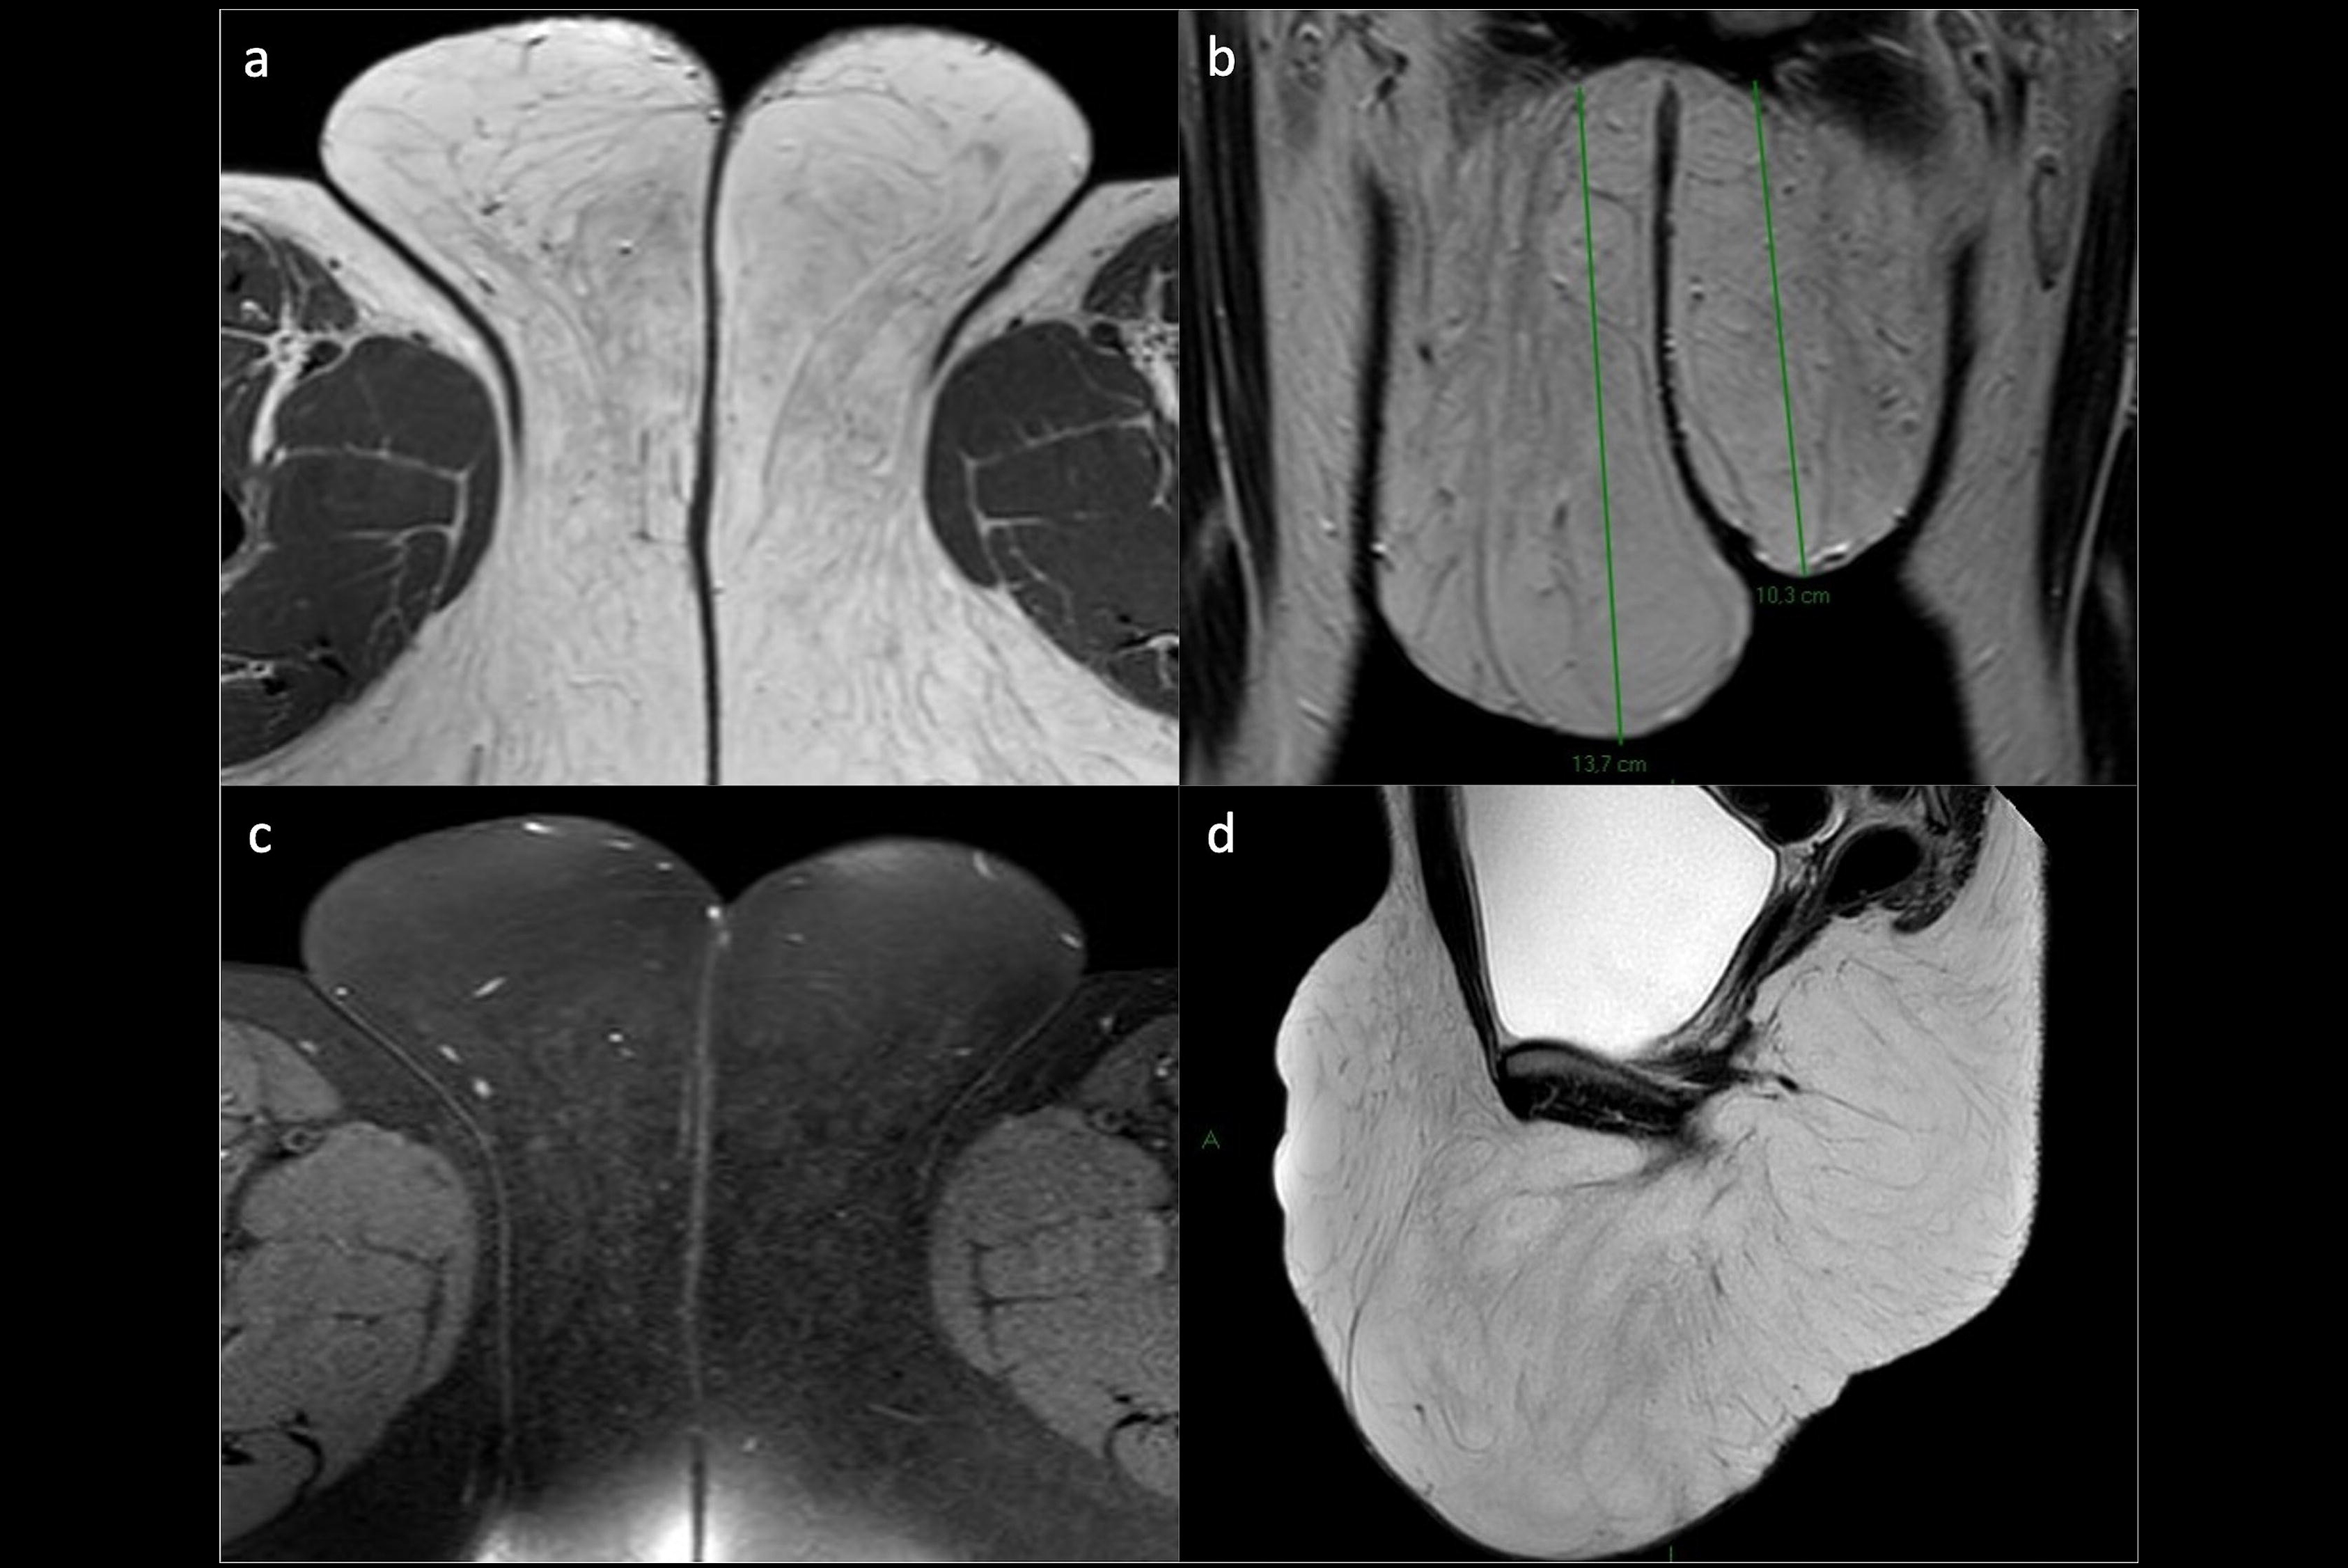

(a) Schematic illustration of International Federation of Gynaecology and Obstetrics (FIGO) stage I. Axial T2-weighted image (b), axial fat saturation T2-weighted image (c) and diffusion-weighted imaging with b-value = 800 s/mm2. (d) shows a vulvar tumor measuring < 2 cm, with pathologic proven stromal invasion of 4 mm, corresponding to FIGO stage IB. All images courtesy of Dr. Olivera Nikolić and Insights into Imaging."In spite of that, MRI staging of vulvar cancer is not used routinely in all cancer centres," the group's chair, Dr. Olivera Nikolić of the University of Novi Sad, Serbia, and colleagues wrote in an article published on 22 September in Insights into Imaging. "Standardising image acquisition techniques and MRI interpretation reduces ambiguity and ultimately improves the contribution of radiology to the staging and management of patients with vulvar cancer."